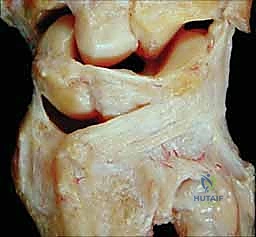

2. كسور رأس الزند (Ulnar Head Fractures)

رأس الزند هو الجزء المفصلي الدائري الذي يدور حوله الكعبرة.

* كسور مفصلية (Articular Fractures): تمتد خطوط الكسر لتشمل الغضروف المفصلي. إذا لم يتم إعادة العظام إلى وضعها التشريحي المثالي (Anatomic Reduction)، فإن المريض سيكون عرضة للإصابة بخشونة المفاصل المبكرة (Post-traumatic Osteoarthritis) وفقدان القدرة على تدوير الساعد.

* كسور غير مفصلية: تقع تحت السطح المفصلي مباشرة، ولكنها قد تؤدي إلى تشوه في زاوية رأس الزند.

صورة لكسر في رأس الزند